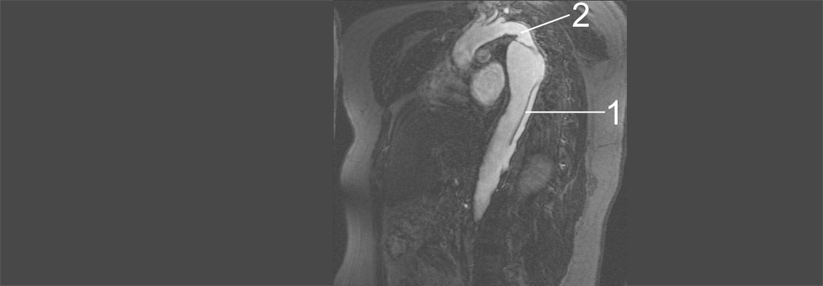

Diese 3D-Rekonstruktion aus der CT-Angiografie zeigt eine ausgedehnte Dissektion der thorakalen Aorta. Diese 3D-Rekonstruktion aus der CT-Angiografie zeigt eine ausgedehnte Dissektion der thorakalen Aorta. © Science Photo Library/Living Art Enterprises

Es gab in den letzten Jahren viele Bestrebungen, um diese Krankheiten so präzise wie möglich zu klassifizieren, zum Beispiel Dissektionen. Bei einer Dissektion Typ A nach der Stanford-Klassifikation ist die Aorta ascendens beteiligt. Sie stellt immer einen herzchirurgischen Notfall dar, betonen die Autoren der aktuellen Leitlinie. Dissektionen im Aortenbogen gehören im Prinzip zum Typ B. Doch diese treten überwiegend distal des Abgangs der linken A. ­subclavia auf, sodass der Aortenbogen selten beteiligt ist. Studienergebnisse mit Typ-B-Dissektionen können daher nicht unbedingt auf Einrisse des Aortenbogens übertragen werden. Für diese wurde der Begriff Non-A-Non-B-Dissektion geschaffen.

Goldstandard in der bildgebenden Diagnostik sind Computertomografie und CT-Angiografie (CTA). Auch eine MRT-Untersuchung leistet gute ­Dienste.